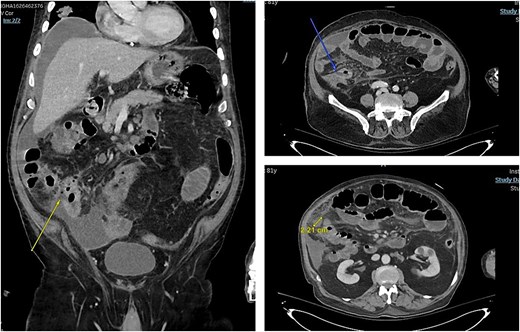

In 2025, he presented to the emergency department (ED) with a 3-week history of persistent diarrhea, lethargy, and vomiting. At presentation, he had no features of active pneumonia and was on room air. Abdominal computed tomography (CT) was done and it showed partial small bowel obstruction with perforated terminal ileum, could be related to underlying ischemia or metastatic involvement. Peritoneal fluid can be appreciated in CT scan (Fig. 1).

Overall findings were in keeping with progressive metastatic disease involving the peritoneum, lymph nodes, liver, and lungs. Family meeting was done to discuss our plan which was urgent surgery. He was taken for exploratory laparotomy, ileocecal resection, and end ileostomy with abdominal washout. Post operatively he was kept in the intensive care unit (ICU) where they did CT chest since he was difficult to wean off oxygen and it showed - multiple bilateral lung nodules and masses with enlarged intrathoracic lymph nodes, considering patient history of bladder cancer and recent CT abdomen findings, chest findings are in keeping with metastasis.